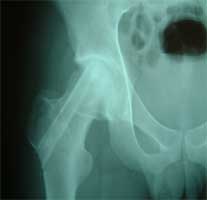

股骨头缺血性坏死MRI显示坏死区          微创手术方法,采用隧道减压刮除死骨